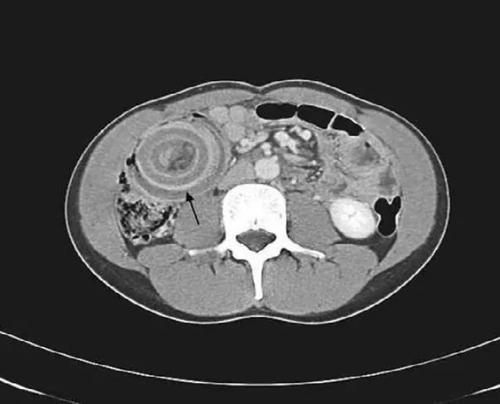

接診醫(yī)生根據(jù)孩子病史、癥狀和體征,考慮腸套疊可能性大,于是給患兒做了超聲,超聲橫斷面上呈“大環(huán)套小環(huán)”的征象。醫(yī)生立即給孩子進(jìn)行空氣灌腸復(fù)位,治療很成功。隨后,童童被收治入院,進(jìn)行進(jìn)一步治療。經(jīng)過(guò)及時(shí)對(duì)癥治療,目前孩子順利康復(fù)出院。

腸套疊,是嬰兒期最常見的急腹癥之一!顧名思義就是腸子套腸子,一段腸管連同其相應(yīng)的腸系膜套入臨近腸腔內(nèi)。嬰幼兒以急性腸套疊發(fā)作為主,兒童期腸套疊發(fā)作以慢性腸套疊為主。此時(shí)孩子出現(xiàn)的肚子疼情況,可不僅僅是喝點(diǎn)熱水或是吃壞了東西那么簡(jiǎn)單。